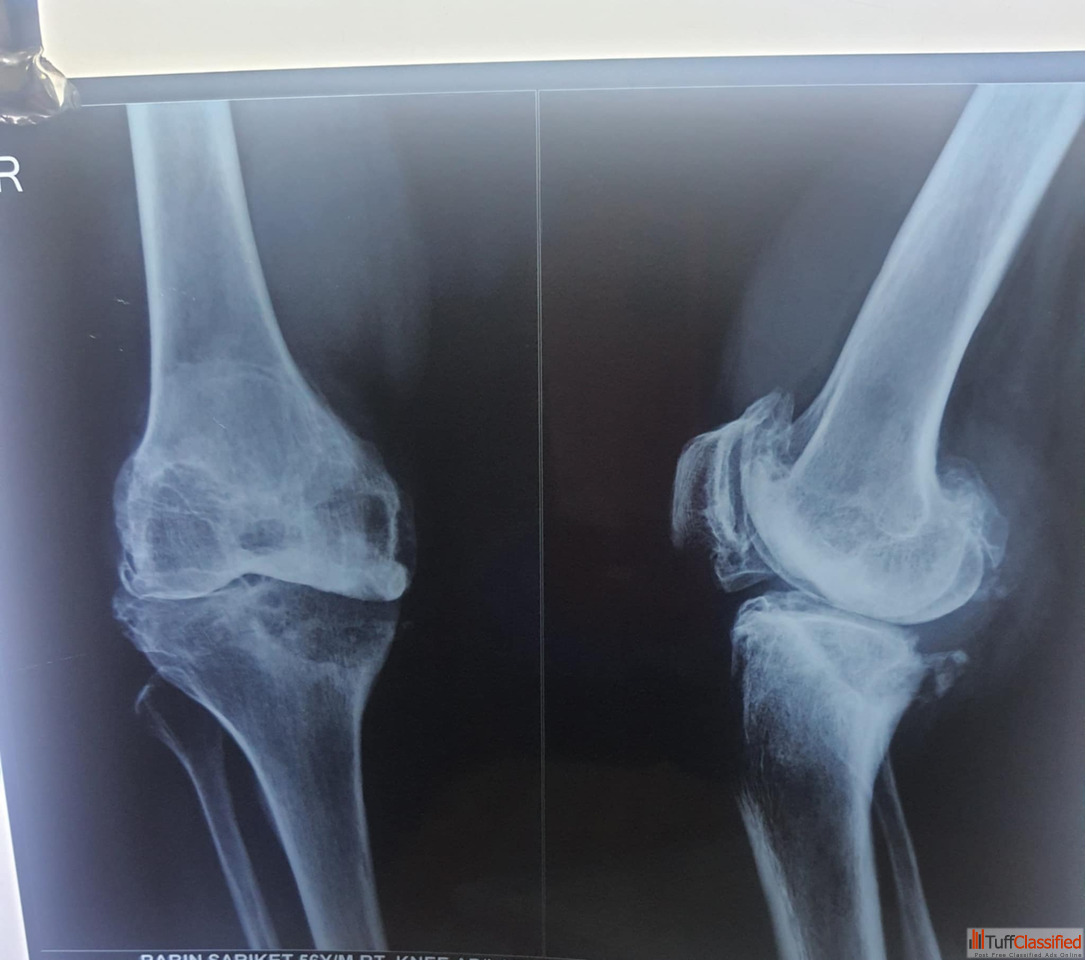

It depends on what kind of fracture you have and where it is. If you have a hairline Fracture or a stress Fracture you might just need to rest and not move that part of your body. If you have a stable Fracture, you might need a cast or a splint. If you have a Fracture, you might need someone to move the bone back into place and then you need a cast. If you have a compound or complex Fracture you might need surgery to fix it with plates or rods or screws. A Fracture treatment doctor in Kolkata will look at your x-rays and tell you what to do.